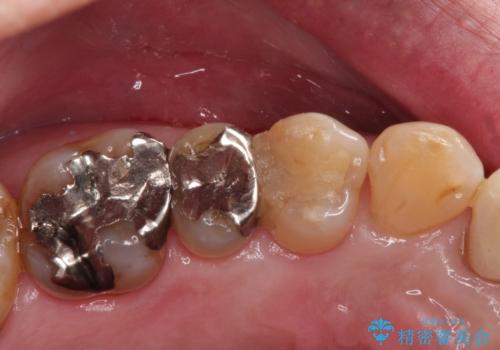

- 銀歯が取れたことを主訴に来院されました。

虫歯も認め、虫歯を除去したのちセラミックインレーにて修復しております。